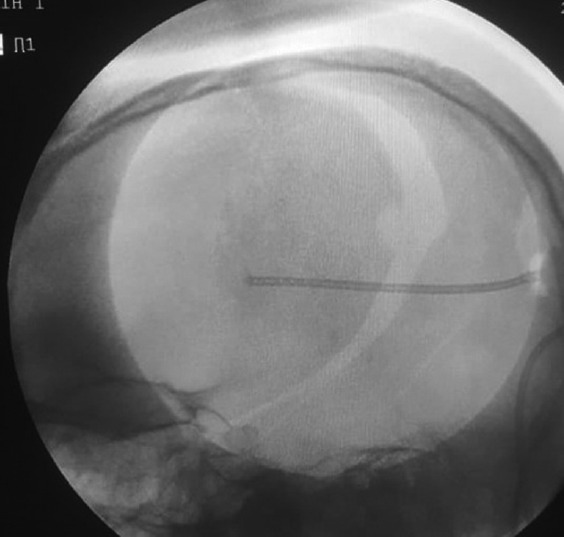

Background: Ventricular catheter (VC) misplacement is one of the most common causes of ventriculoperitoneal (VP) shunt malfunction and revision surgery. Most of the VC placements are done by freehand method. We evaluated the use of intraoperative fluoroscopy for assessing VC placement.

Materials and methods: A total of 70 patients were enrolled in the study. Patients with hydrocephalus who required cerebrospinal fluid diversion were enrolled in the study. Thirty-five patients were placed in the control group (patients in whom intraoperative fluoroscopy was not done), and 35 patients were placed in the test group (patients in whom intraoperative fluoroscopy was done). Patients with trapped ventricles and multiloculated hydrocephalus were excluded from the study. VP shunt insertion was done through standard Keen's point.

Results: The positioning of VC was optimal in 40 patients, with a significant difference between the test group and the control group. Gross malpositioning was seen in seven patients: four in the test group and three in the control group. All gross malpositioned VCs in the test group were corrected intraoperatively. VC crossing midline was less in the test group as compared to the control group.

Conclusion: Fluoroscopy is an easy and cheap method to assess VC position intraoperatively. It is readily available and helps us in avoiding resurgery due to VC misplacement and subsequent blockage.